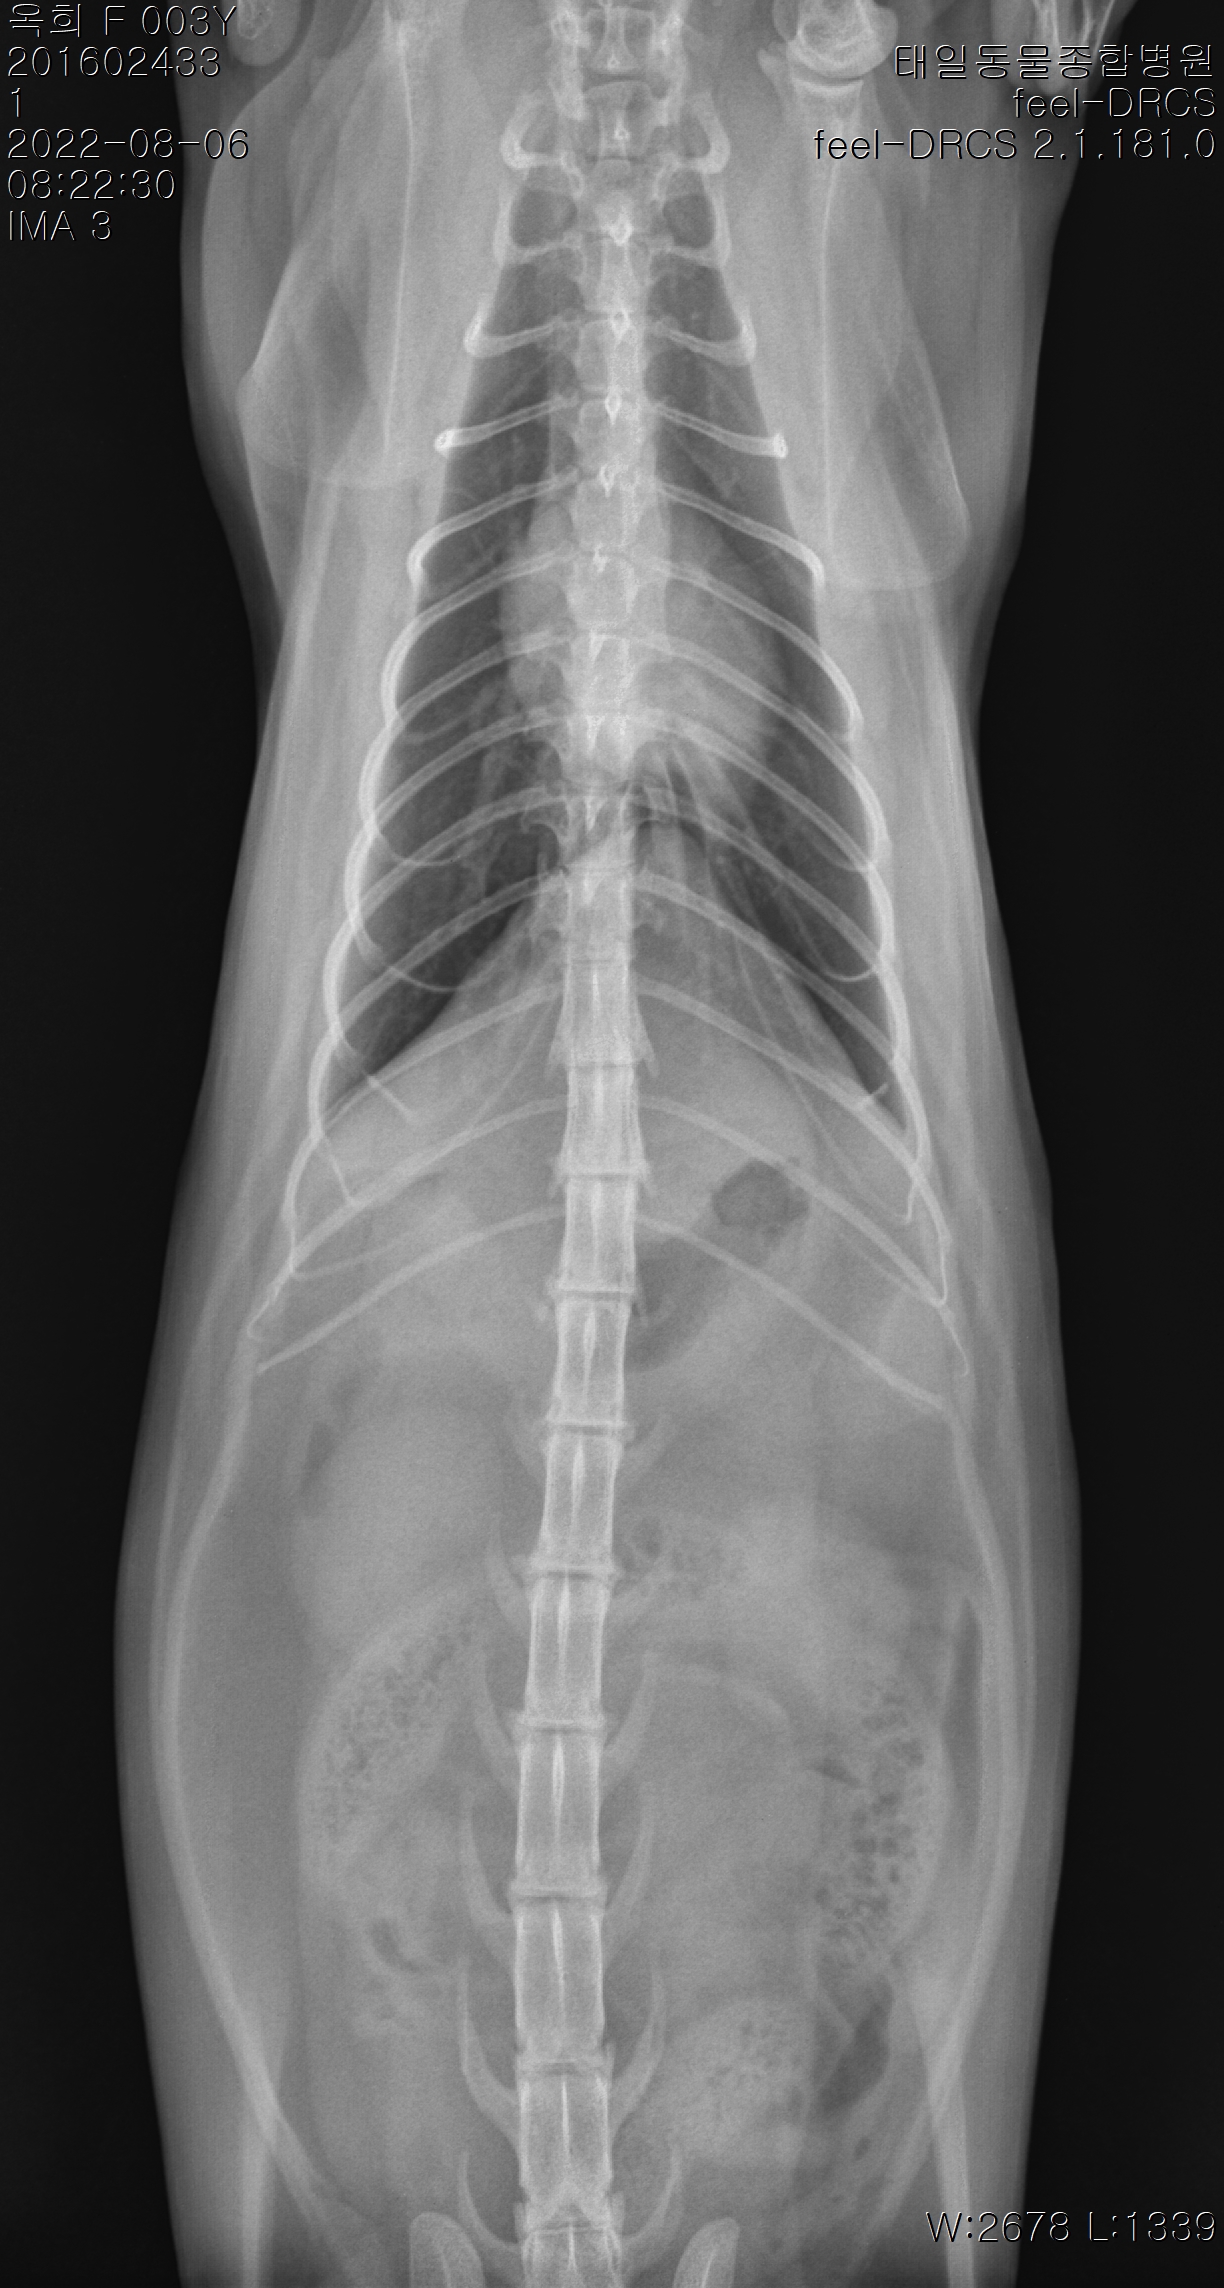

옥희(몰랑이)랑 복희(동백이)는 아주 잘 지내고 있습니다.옥희는 여전히 터널에서 노는 거 좋아하고 캣휠탈때는 꼭 저를 불러서 옆에서 보라고 해요~복희는 이제 진짜 완전히 마음의 문을 활짝 열어준 거 같아요.곧잘 옥희한테 먼저 장난도 치고 저희옆에 꼭 붙어 지냅니다.작년 8월에는 종합검진을 받았는데 옥희는 예전에 고관절 골절 흔적이 있단 얘기를 들었어요.그 순간 놀래기도 하고 어디서 누구한테 그런일을 당했던건지 상상하게 되면서 마음이 너무 아프더라고요.지금은 치료해줄 부분이 아니고 잘 지내고 있어서 다행이긴 합니다.복희는 심장관련 혈액검사결과가 살짝 높게 나와서 한달후 심장초음파 검사 재검해봤는데 심장이 커졌다거나 하는 문제가 없다고 했어요~아이들도 잘 지내고 저희도 애기들 덕분에 즐겁게 살고 있습니다^^다음에 또 즐거운 소식과 사진 올릴게요~